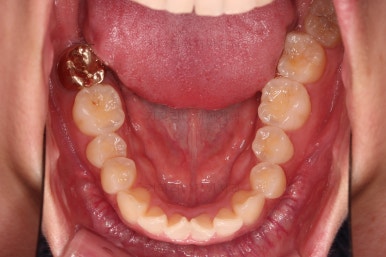

1. 초진

초진 시 입안의 모습입니다.

어금니 쪽은 약간 삐뚤긴 하지만 꼭 교정해야 할 정도는 아니고, 불편감 없이 비교적 잘 맞물리는 상태였습니다.

다만, 앞니ㅉㄱ이 공간이 부족해서 중간 치아들이 많이 회전되어있는데, 이를 환자분들의 표현에 따르면 "나비치아" 라고 부릅니다.

위아래 중간 앞니가 모두 나비치아처럼 되어있고요.

윗니가 아랫니보다 앞쪽으로 나와 있는 모습에 아래앞니가 윗니쪽으로 깊숙이 올라간 "과개교합" 양상을 보였습니다.